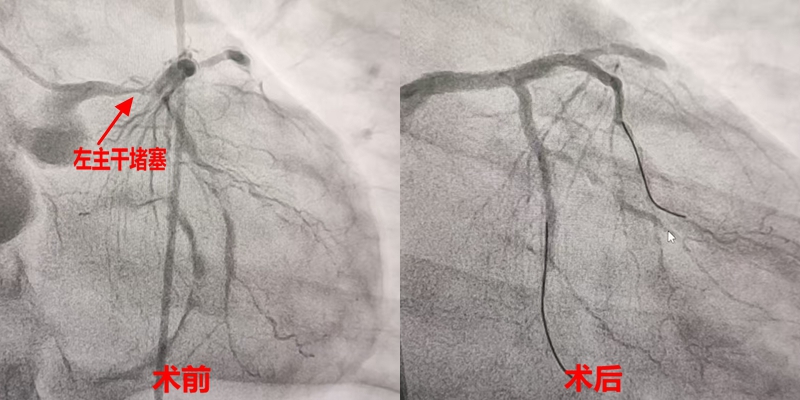

“患者依赖ECMO维持生命,手术不能有丝毫差错!”心血管内科主任阮宏标带领团队,在影像引导下谨慎操作。当造影结果显示:张叔三支冠状动脉均严重病变,左主干(心脏“供血主干道”)狭窄程度高达99%时,在场所有人都倍感压力。

凭借精湛技艺,团队缓慢将导丝穿过狭窄处,球囊扩张、支架释放一气呵成。当造影剂顺畅流过左主干,张叔紊乱的心律逐渐恢复正常,心脏“生命线”成功打通!